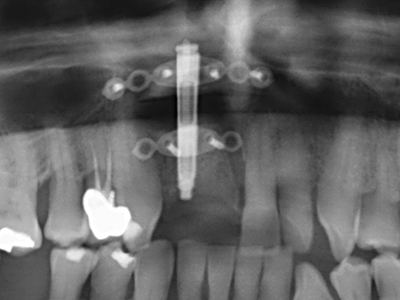

Die Präparation des lateralen Fensters bei der externen Sinusbodenelevation stellt gerade für chirurgisch unerfahrene Implantologen eine große Herausforderung dar. Die knöcherne Bedeckung der Kieferhöhle ohne eine Verletzung der darunterliegenden Schneider’schen Membran abzutragen ist dabei nur ein Teil der Operation – nach Schaffung eines ausreichenden Zugangs muss die Kieferhöhlenschleimhaut vorsichtig mobilisiert werden, um Raum für das einzubringende Material bzw. die Implantate zu schaffen. In dieser Indikation ist die Piezochirurgie zweierlei hilfreich: zum einen kann durch Verwendung diamantierter Instrumente eine selektive Knochenabtragung erfolgen und die darunter liegende Schleimhaut bleibt bei vorsichtiger Vorgehensweise intakt. Zum anderen unterstützen die Ultraschallfrequenzen zusätzlich eine komplikationslose Ablösung der Schleimhaut – sie werden durch spezielle stumpfe Ansätze in den Spaltraum zwischen Schleimhaut und Kieferhöhlenboden übertragen (Cassetta, Ricci et al. 2012, Pereira, Gealh et al. 2014) (Rickert, Vissink et al. 2013). So erscheint es nicht verwunderlich, dass in aktuellen Übersichtsarbeiten über die externe Sinusbodenelevation neben der Verwendung von rauen Implantatoberflächen und dem Einsatz von Knochenersatzmaterialien auch der Einsatz von piezoelektronischen Geräten als positiv bewertet wird (Wallace, Tarnow et al. 2012).